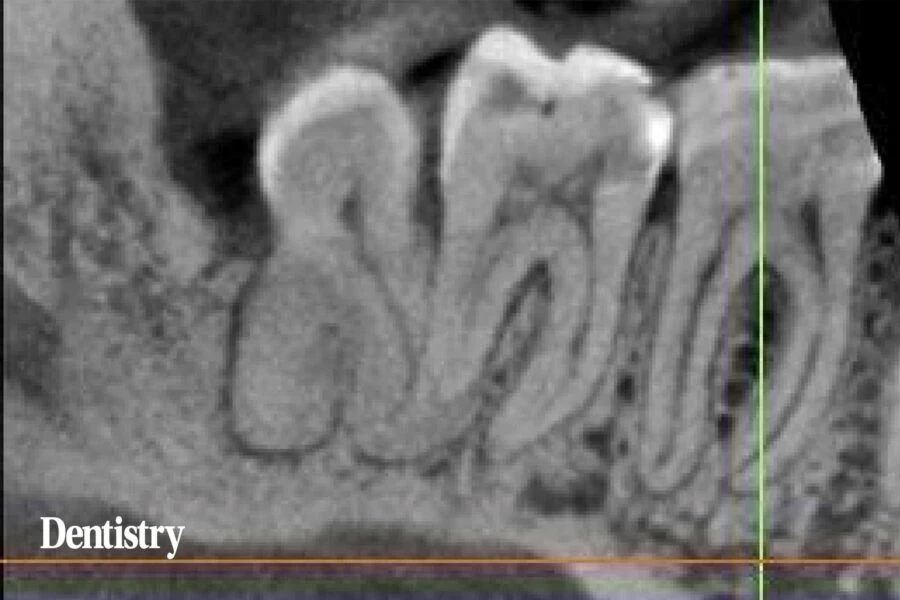

Về mặt lâm sàng, răng chịu được lực khi gõ. Không có đau ở rãnh lợi và độ sâu thăm dò trong giới hạn bình thường. Chụp CBCT là cần thiết để kiểm tra xem có bệnh lý liên quan đến chóp răng nào không trước khi bắt đầu điều trị tủy răng.

Răng LR6 này có ống tủy thông suốt, chiều rộng dây chằng nha chu bình thường và lớp màng cứng. Lời giải thích hợp lý nhất cho cơn đau là do tủy răng không còn sống hoặc gãy chân răng. Nhưng không thấy gãy chân răng.

Lát cắt toàn cảnh của Răng cối hàm dưới từ số 6-8 và mặt cắt ngang của vùng LR6 cho thấy ống tủy, chiều rộng dây chằng nha chu bình thường và lớp màng cứng. Cũng có thể thấy không gian nang mở rộng liên quan đến LR8.